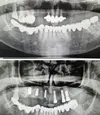

Implant tedavisi